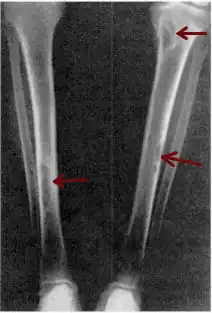

| Osteitis fibrosa cystica of the tibia. Arrows point to the brown tumors which are typically present in bones of people with OFC. | |

Osteitis fibrosa cystica (/ˌɒstiˈaɪtɪs faɪˈbroʊsə ˈsɪstɪkə/ OSS-tee-EYE-tis fy-BROH-sə SIS-tik-ə) is a skeletal disorder resulting in a loss of bone mass, a weakening of the bones as their calcified supporting structures are replaced with fibrous tissue (peritrabecular fibrosis), and the formation of cyst-like brown tumors in and around the bone. Osteitis fibrosis cystica (OFC), also known as osteitis fibrosa, osteodystrophia fibrosa, and von Recklinghausen's disease of bone (not to be confused with von Recklinghausen's disease, neurofibromatosis type I), is caused by hyperparathyroidism, which is a surplus of parathyroid hormone from over-active parathyroid glands. This surplus stimulates the activity of osteoclasts, cells that break down bone, in a process known as osteoclastic bone resorption. The hyperparathyroidism can be triggered by a parathyroid adenoma, hereditary factors, parathyroid carcinoma, or renal osteodystrophy. Osteoclastic bone resorption releases minerals, including calcium, from the bone into the bloodstream, causing both elevated blood calcium levels, and the structural changes which weaken the bone. The symptoms of the disease are the consequences of both the general softening of the bones and the excess calcium in the blood, and include bone fractures, kidney stones, nausea, moth-eaten appearance in the bones, appetite loss, and weight loss.

X-rays may also be used to diagnose the disease. Usually, these X-rays will show extremely thin bones, which are often bowed or fractured. However, such symptoms are also associated with other bone diseases, such as osteopenia or osteoporosis.[29] Generally, the first bones to show symptoms via X-ray are the fingers.[22] Furthermore, brown tumors, especially when manifested on facial bones, can be misdiagnosed as cancerous.[29] Radiographs distinctly show bone resorption and X-rays of the skull may depict an image often described as "ground glass" or "salt and pepper".[30][31] Dental X-rays may also be abnormal.[2]

The brown tumors commonly associated with OFC display many of the same characteristics of osteoclasts.[23] These cells are characteristically benign, feature a dense, granular cytoplasm, and a nucleus that tends to be ovular in shape, enclosing comparatively fine chromatin. Nucleoli also tend to be smaller than average.[18]